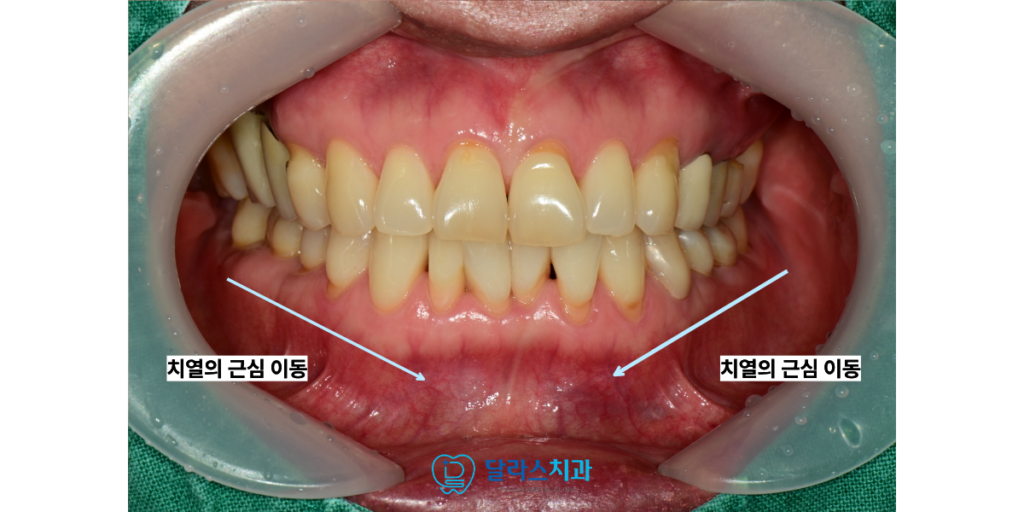

특히 치아는 평생에 걸쳐 조금씩 앞쪽으로 이동하려는

성질을 가지고 있는데 이를 치열의 근심 이동이라고 부릅니다.

이러한 현상이 지속되면 가지런했던 치아들이

서로 겹치거나 뒤틀리는 현상이 나타나게 됩니다.

이번에 저희 노원치과 달라스치과를 방문해 주신 60대여성 환자분의

사례를 통해 이러한 부분 교정의 실제 과정을 자세히 설명해 드리겠습니다.

환자분께서는 세월이 흐르며 아래쪽 앞니들이 점점

겹쳐지는 현상으로 인해 불편함을 느끼고 계셨습니다.

검진 결과 하악 앞니 부위에 전형적인 치열 겹침 현상이 진행되고 있었으며

이로 인해 해당 부위의 잇몸 관리가 원활하지 않아 염증이 반복되는 상태였습니다.